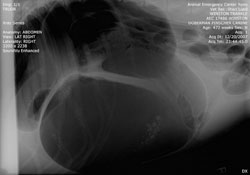

X-ray of a Gastric Torsion (GDV)

We have a state of the art Digital X-Ray Machine. Digital radiographs have revolutionized veterinary radiology by increasing the speed in which x-rays can be obtained and by providing better quality images. Another advantage of Digital Radiographs is that we can easily send in our x-rays for a Board Certified Radiologist to review increasing the quality of x-ray interpretation.